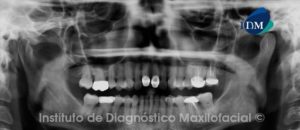

Paciente masculino, 11 años de edad es referido al Instituto de Diagnostico Maxilofacial (IDM) para evaluación general.A la evaluación de la radiografía panorámica (ortopantomografía) se